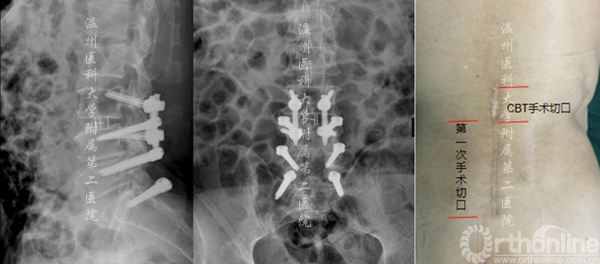

案例3

腰4-骶1行Dynesys术后3年,腰3.4椎管狭窄。

术后X线资料(左侧)及术后切口对比(右侧)